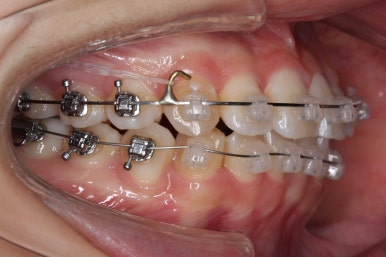

연산동교정치과에서 이번에 진행한 방법은 비발치교정이기 때문에 미니스크류를 잇몸뼈에 식립합니다.

위 사진에서 화살표 부분이 미니스크류인데요.

어금니쪽 잇몸에 아주 작은 나사가 보이실텐데요. 이것을 이용해서 전체 치열을 뒤로 당겨넣습니다. 물론 사랑니는 제거가 된 상태입니다.

윗니를 계속 당겨 넣습니다.

만족을 하실 때까지 계속계속 넣고 그리고 입 안에서는 허락하는 만큼 계속 당겨 넣습니다.

이제 아래쪽도 당겨 넣습니다.

원하는 만큼, 허락하는 만큼 계속 당겨 넣습니다. 연산동교정치과에서는 비발치 돌출입 교정을 위해 총 4개의 미니스크류를 식립했습니다.